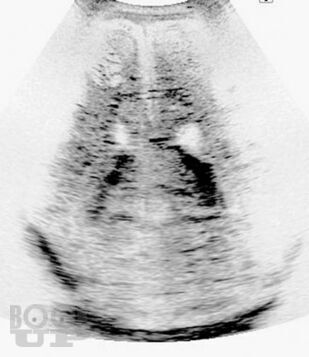

Это первая отечественная книга по патологии головного мозга у новорожденных и детей раннего возраста. Книга состоит из 7 глав, в которых рассмотрены вопросы развития головного мозга во внутриутробном периоде, этиология, патогенез, патоморфология и клинические проявления основных поражений мозга, а также внутричерепные кровоизлияния и пороки развития, в том числе уникальные. В книге также изложены новые и дискуссионные вопросы диагностики заболеваний, приведены классификации поражений, уточнены вопросы нозологии в детской неврологии, которые изучены недостаточно. Читатель получит сведения о том, насколько велико разнообразие форм поражений головного мозга у детей, как эти поражения отличаются от патологии мозга у взрослых и какова роль инфекций, гипоксии, родовой травмы и других факторов в их происхождении. Текст сопровождают более 450 цветных иллюстраций (фотографии, схемы и графики). Книга предназначена для патологов, педиатров, акушеров, перинатологов, инфекционистов, детских невропатологов, неонатологов, реаниматологов, специалистов нейровизуализационных методов исследования и судмедэкспертов. Книга может служить учебным пособием или справочником по основным заболеваниям головного мозга у новорожденных и детей раннего возраста.